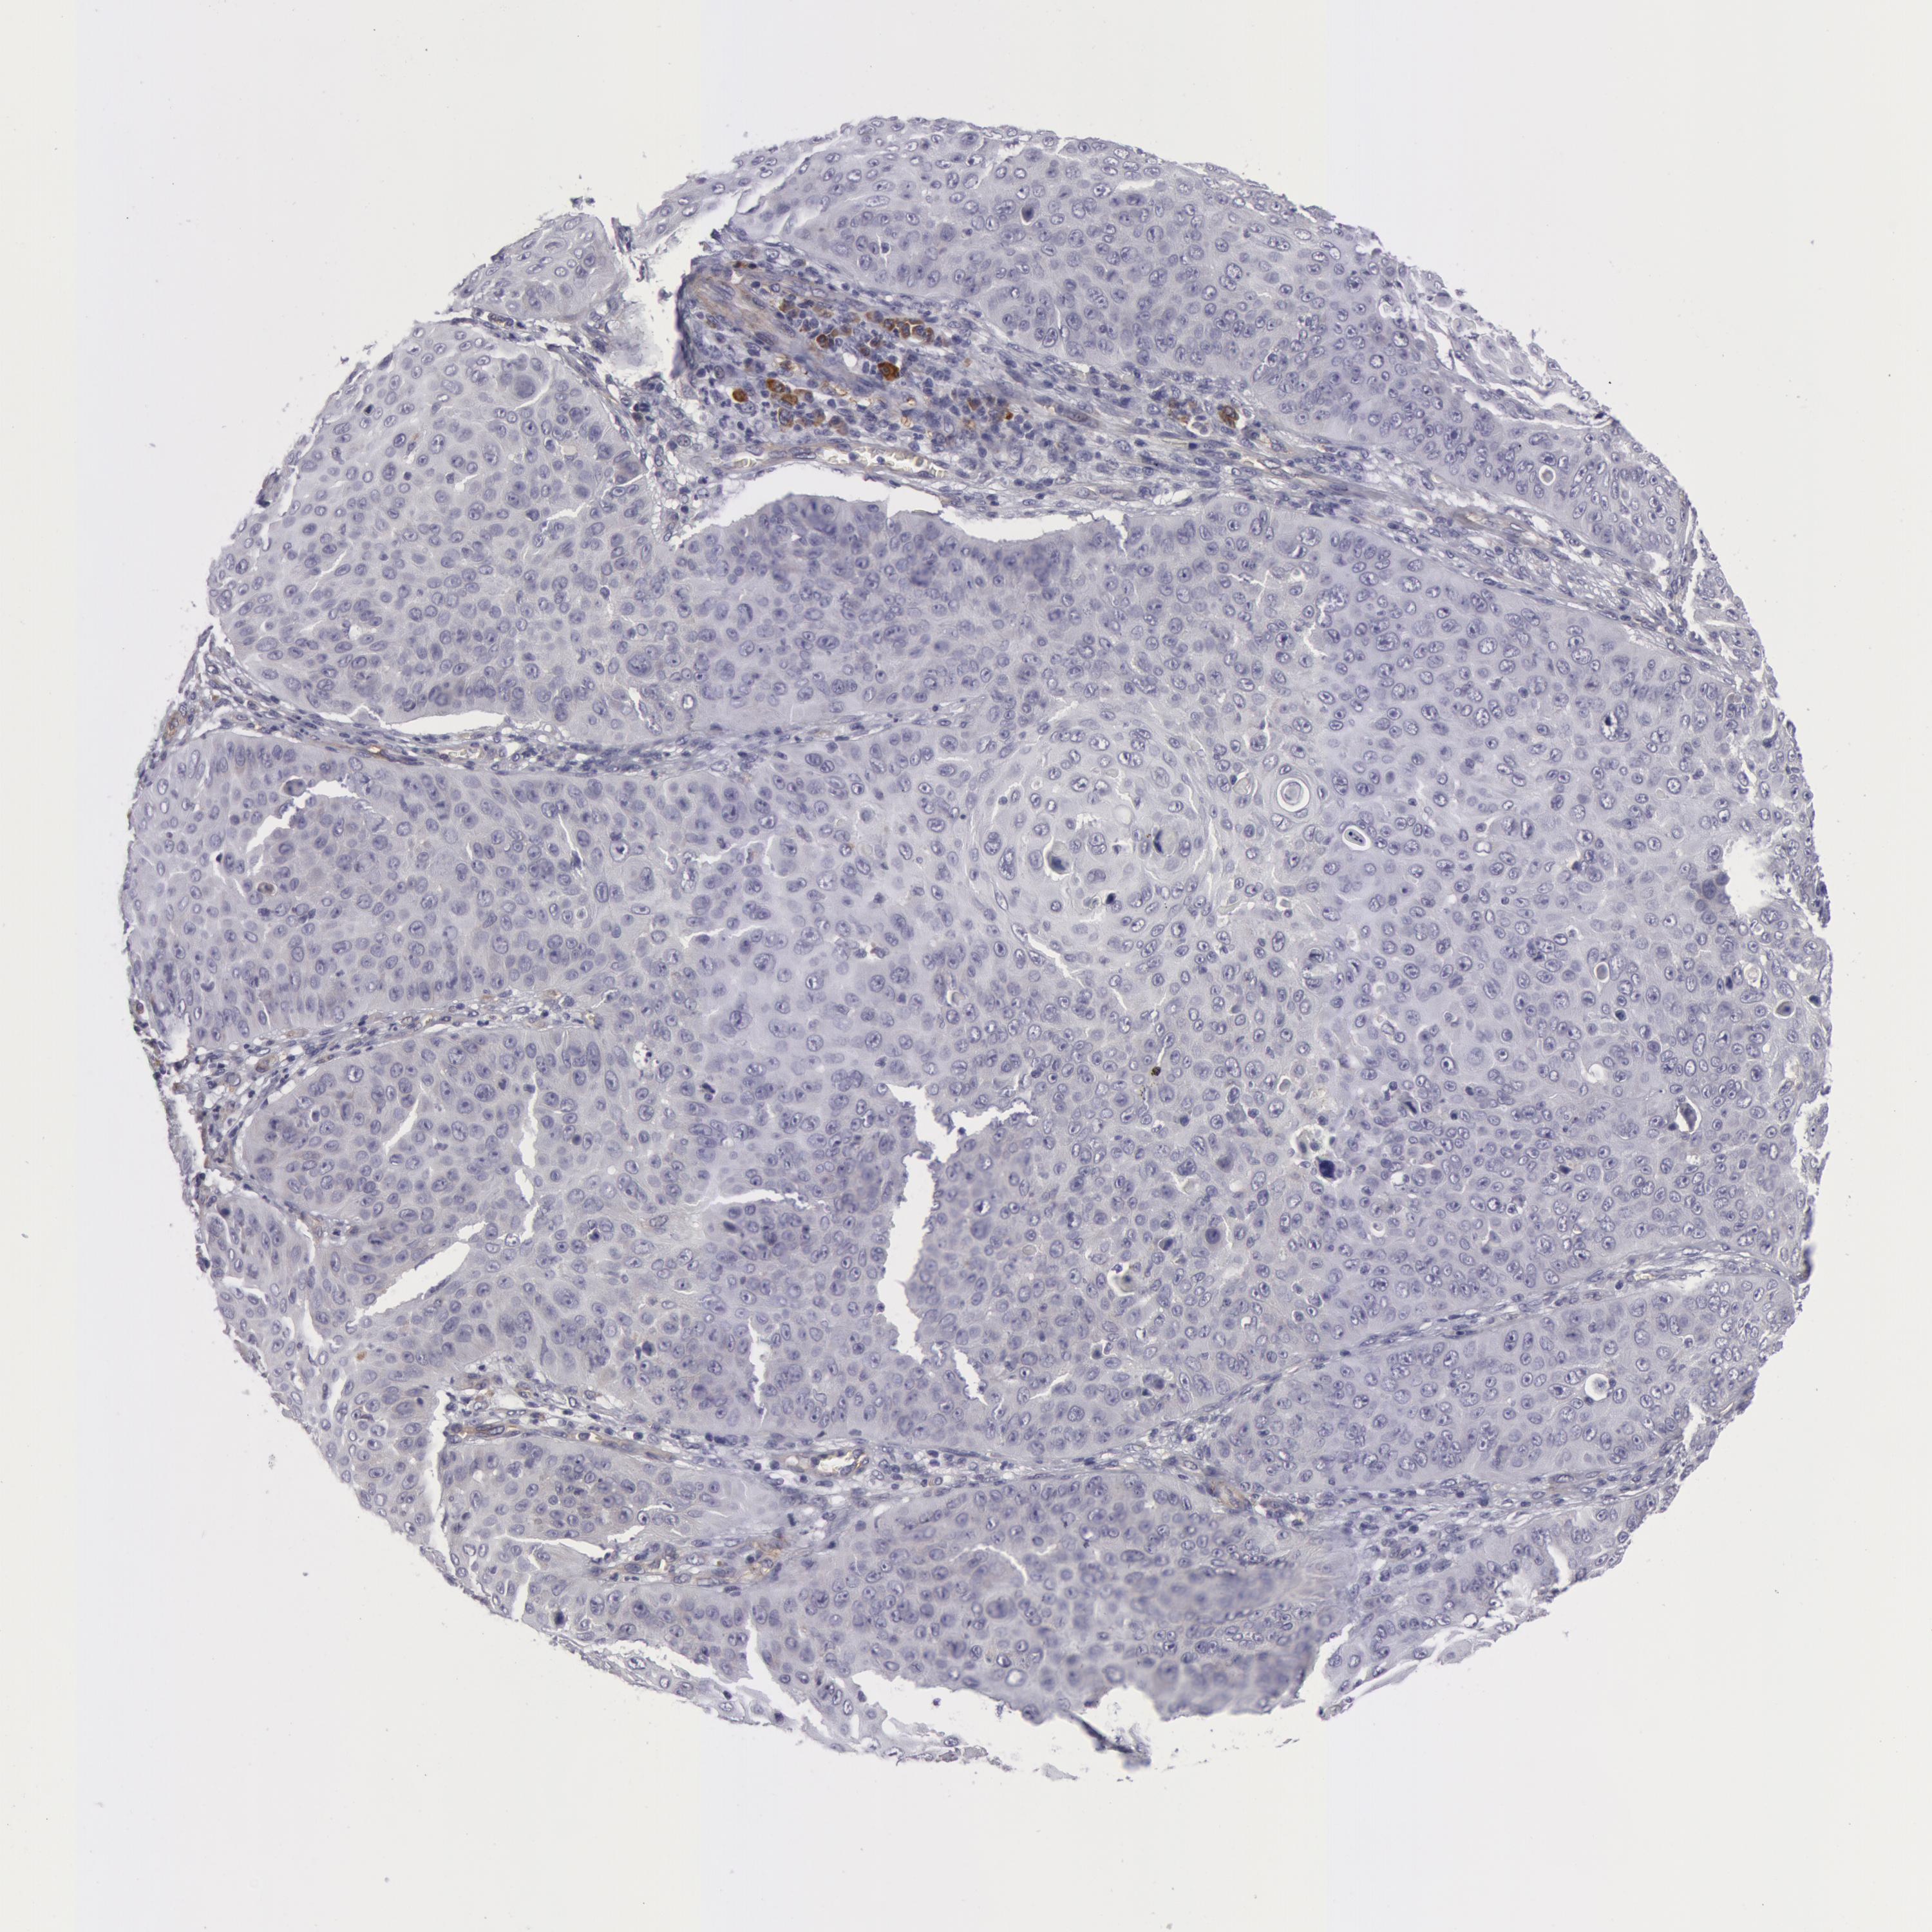

SKIN CANCER - Protein expressioni

A mouse-over function shows sample information and annotation data. Click on an image to view it in a full screen mode. Samples can be filtered based on level of antibody staining by selecting one or several of the following categories: high, medium, low and not detected. The assay and annotation is described here.

Antibody stainingi

Antibody staining in the annotated cell types in the current human tissue is reported as not detected, low, medium, or high, based on conventional immunohistochemistry profiling in selected tissues. This score is based on the combination of the staining intensity and fraction of stained cells.

Each image is clickable and will lead to virtual microscopy that enables deeper exploration of all samples and also displays staining intensity scores, fraction scores and subcellular localization as well as patient and tissue information for each sample.

Antibody HPA001554

Staining

High

Medium

Low

Not detected

Intensity

Strong

Moderate

Weak

Negative

Quantity

>75%

75%-25%

<25%

None

Location

Nuclear

Cytoplasmic/membranous

Cytoplasmic/membranous,nuclear

Squamous cell carcinoma, NOS

Basal cell carcinoma